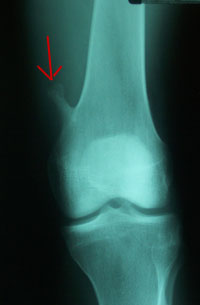

About a year ago, I felt something funny in my left leg. After a couple of runs - Eugene's 10K Butte-to-butte - and other exercises, I started feeling more pain. The pain became more real about 5-6 months ago, so I went to see my doctor. After a couple of X-rays, he said there is a bone growth and he referred me to an orthopedic.

• June 17th 2004 I will have a surgery, "Excision of Osteochondroma Left Femur". It is only a day-surgery and I will not use my leg for a week and thereafter I will be on the crutches I think for few days -- more on this